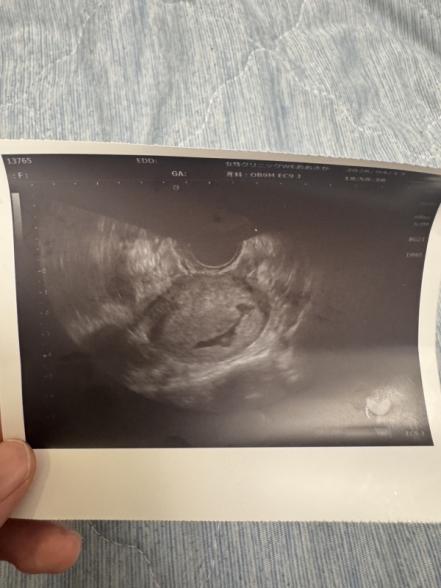

妊娠6週目エコー写真がいびつです

初めまして。 添付させて頂きました写真のようないびつな形の胎嚢でとても不安です。 まだ心拍も確認できておらず。。。 いつも通っているクリニックさんで別で1度通院しました所、胞状奇胎の可能性があると言われ、血液検査しましたが、数値は6週目の今で2200程度でした。 6週目の今の症状はお腹の張り、頭痛、腹痛、吐き気、空嘔吐、眠気と言ったところですが、どれもめちゃくちゃしんどいって感じではないです。 出血もありませんが、大丈夫でしょうか...?

ですが、この1枚のエコーだけで、胞状奇胎かどうかを判断することは難しいです。

ただし、今いただいている情報から見ると、典型的な胞状奇胎っぽさは強くはない印象です。

胞状奇胎の場合は、胎芽は見えづらく、中身が均一じゃなくモヤモヤした像に見えることが多いようです。

胞状奇胎だと多くは、異常に高い値になります。 次回エコーで確認することとしては、胎芽の成長がある、心拍が見える、子宮内の構造が正常かどうかになってきます。